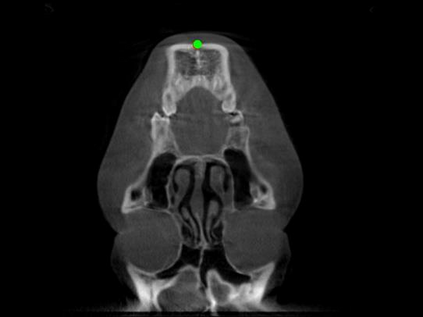

Detecting 3D landmarks on cone-beam computed tomography (CBCT) is crucial to assessing and quantifying the anatomical abnormalities in 3D cephalometric analysis. However, the current methods are time-consuming and suffer from large biases in landmark localization, leading to unreliable diagnosis results. In this work, we propose a novel Structure-Aware Long Short-Term Memory framework (SA-LSTM) for efficient and accurate 3D landmark detection. To reduce the computational burden, SA-LSTM is designed in two stages. It first locates the coarse landmarks via heatmap regression on a down-sampled CBCT volume and then progressively refines landmarks by attentive offset regression using multi-resolution cropped patches. To boost accuracy, SA-LSTM captures global-local dependence among the cropping patches via self-attention. Specifically, a novel graph attention module implicitly encodes the landmark's global structure to rationalize the predicted position. Moreover, a novel attention-gated module recursively filters irrelevant local features and maintains high-confident local predictions for aggregating the final result. Experiments conducted on an in-house dataset and a public dataset show that our method outperforms state-of-the-art methods, achieving 1.64 mm and 2.37 mm average errors, respectively. Furthermore, our method is very efficient, taking only 0.5 seconds for inferring the whole CBCT volume of resolution 768$\times$768$\times$576.